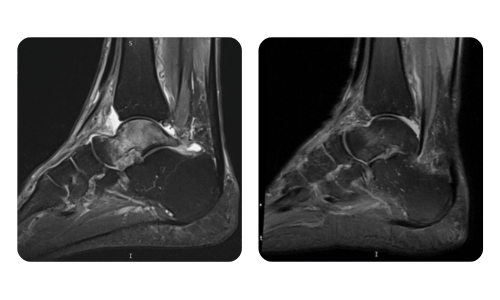

Der Fortschritt unserer Patienten, gemessen vor und nach der hyperbaren Therapie, spiegelt die Effizienz und die positive Wirkung der Behandlung wider. Entdecken Sie dokumentierte Ergebnisse der hyperbaren Therapie in der Klinik Hyperbarium Oradea, basierend auf klinischen Bewertungen und objektiven Daten, die signifikante Verbesserungen bei verschiedenen Erkrankungen belegen.